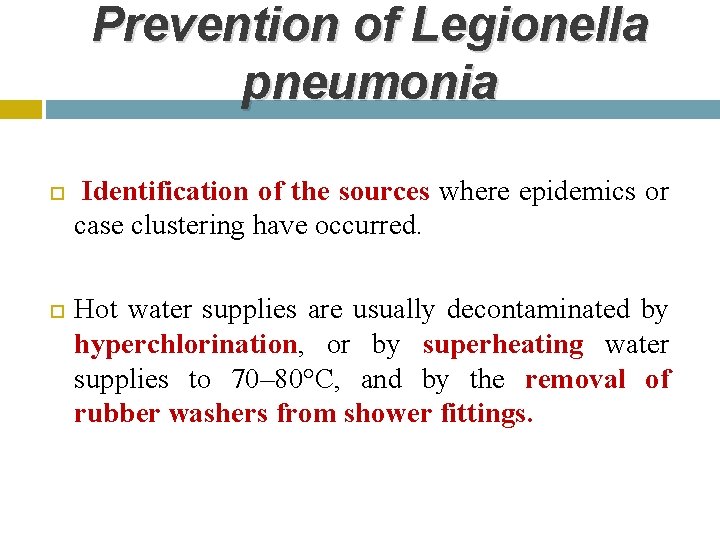

Prevention of Legionella pneumonia Identification of the sources where epidemics or case clustering have occurred. Hot water supplies are usually decontaminated by hyperchlorination, or by superheating water supplies to 70– 80°C, and by the removal of rubber washers from shower fittings.